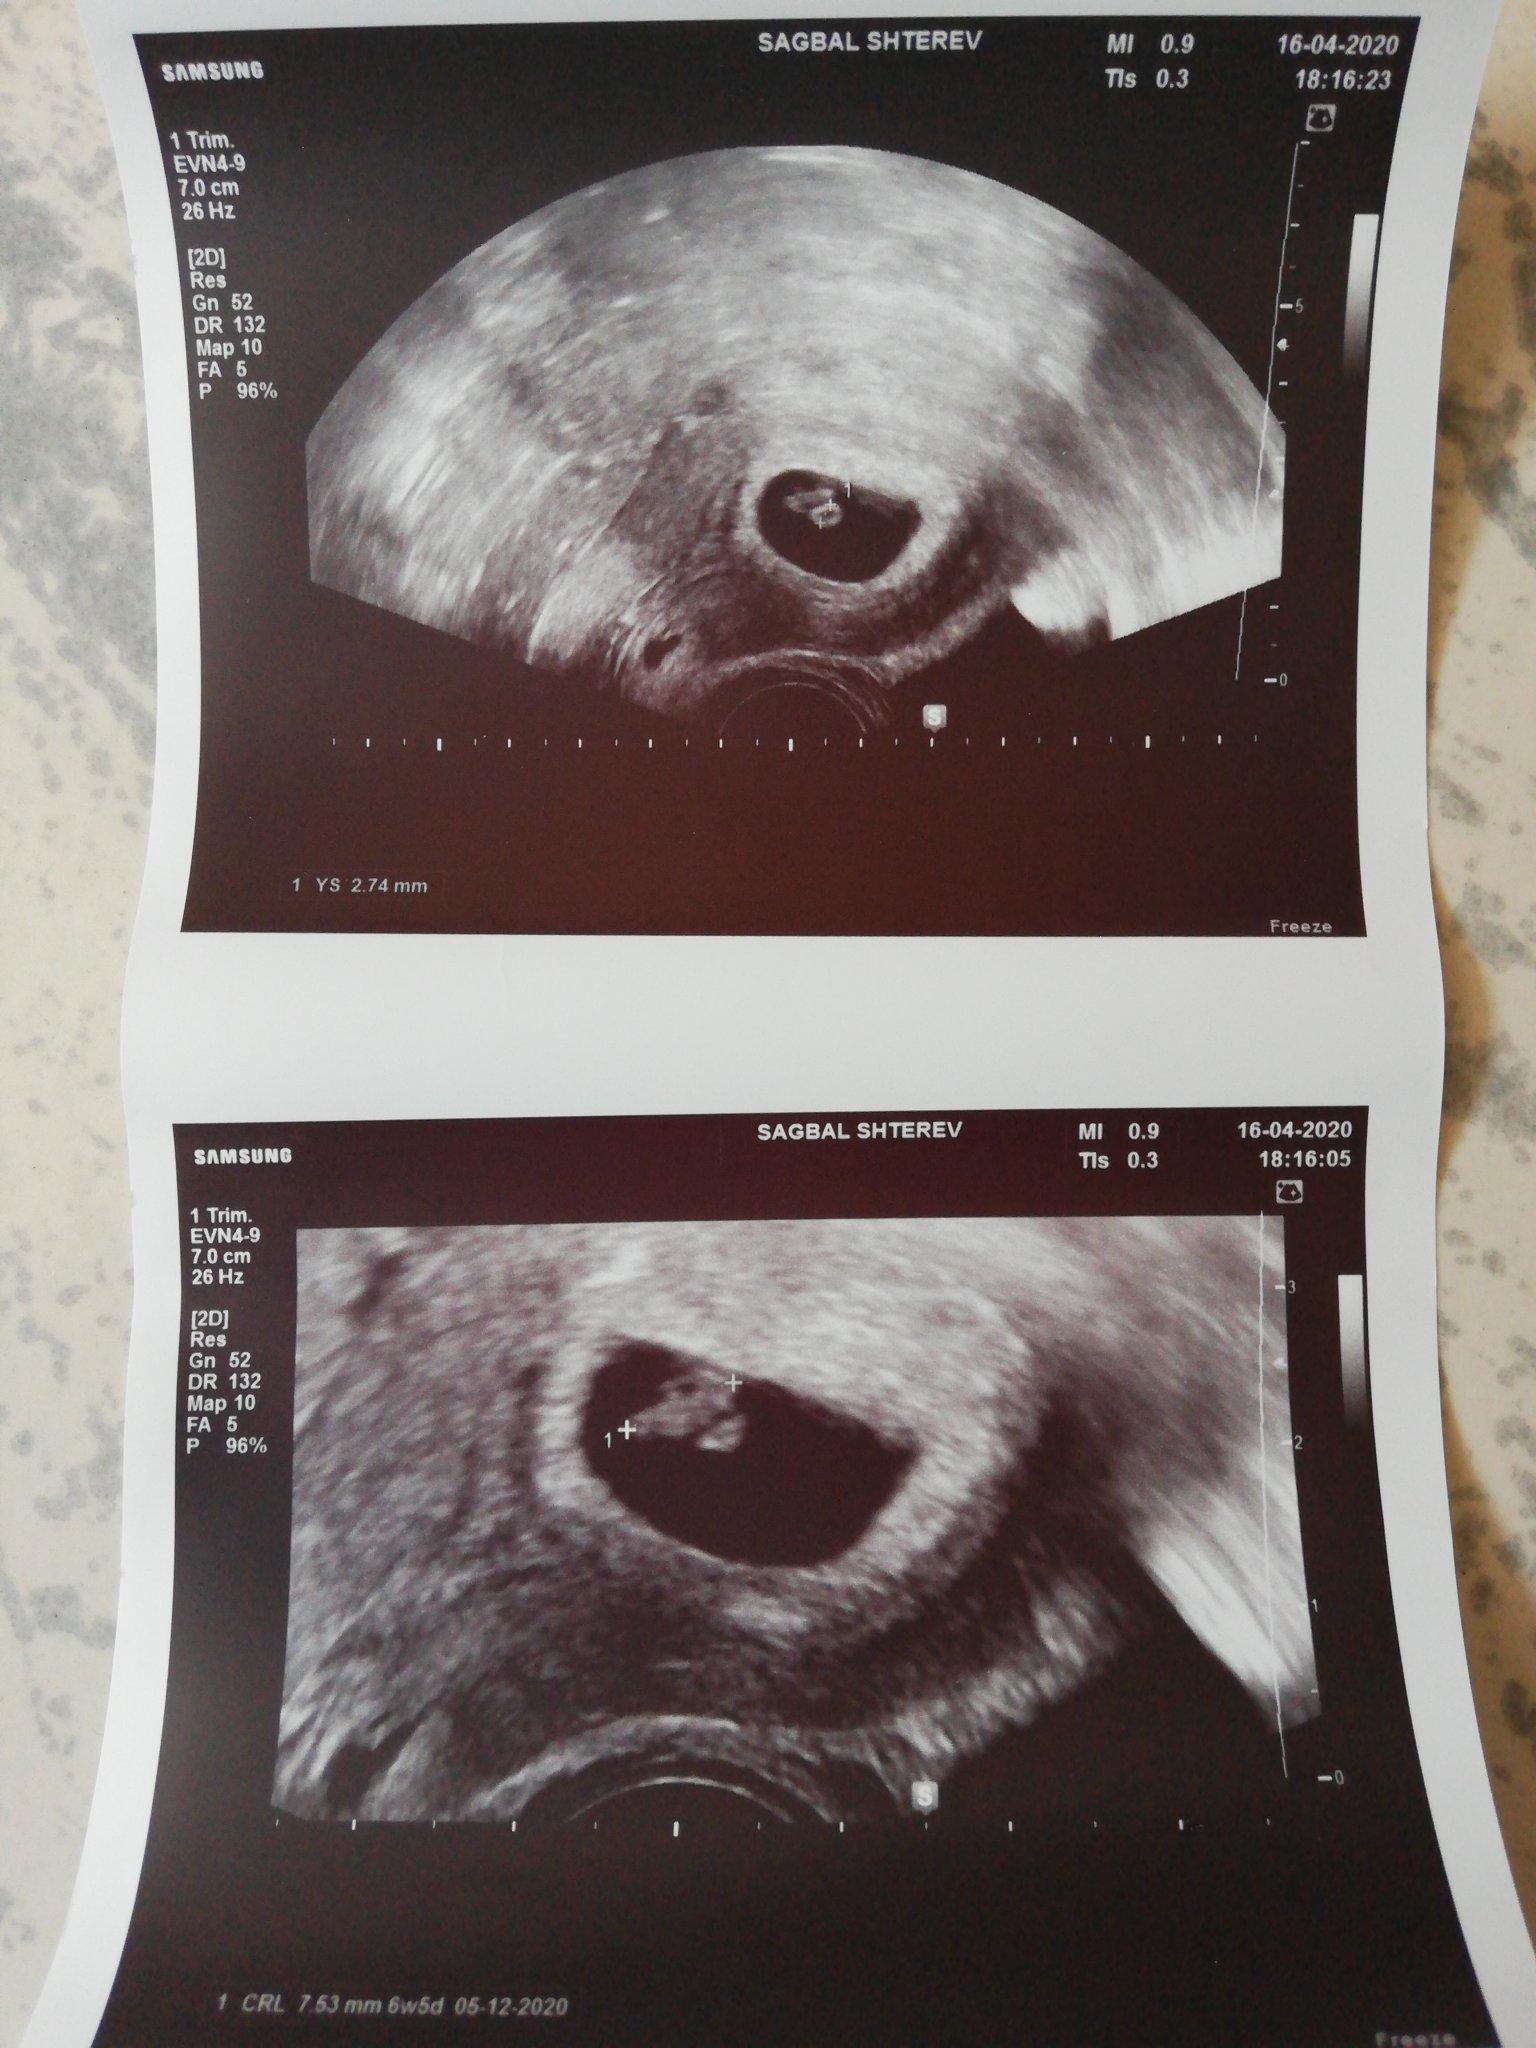

Ето за сравнение мои снимки от 6+4 дни

Последната менструация беше на 23.02 , 36 дне ми е цикъла. Ходих при една лекарка в ДКЦ в нашия град , само да вметна че снимката е от коремен ехограф. Със сигурност апаратурата е по-стара от тази на Щерев ( виждам, че твоите са от там) .

Аз съм 7+3 днес като овулацията ми беше точно на 14 ден, цикъла ми е 25 дни средно. Ти си 7-8 дни преди мен по дата на последен цикъл, не може да си в 10 г.с. Калкулаторите са верни. Ако знаеш вече кога точно е била овулацията, може да сложиш на календара тази дата.